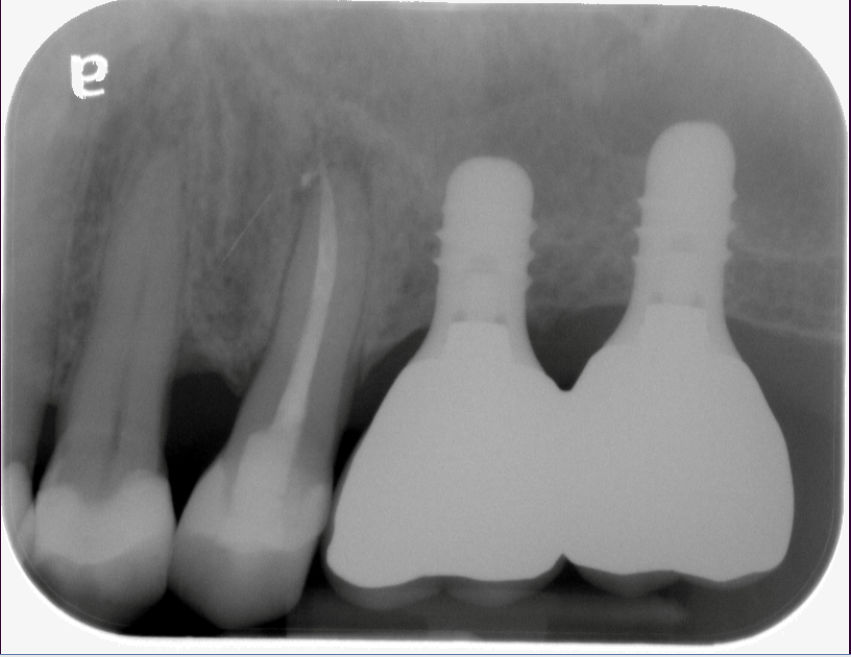

The bone used in a sinus lift may come from your own body (autogenous bone), from a cadaver (allogeneic bone) or from cow bone (xenograft). You will need X-rays taken before your sinus lift so the dentist can study the anatomy of your jaw and sinus. You also may need a special type of computed tomography (CBCT) scan. This scan will allow the dentist to accurately measure the height and width of your existing bone and to evaluate the health of your sinus.

After several months of healing, the bone becomes part of the patient’s jaw and dental implants can be inserted and stabilized in this new sinus bone.

If enough bone between the upper jaw ridge and the bottom of the sinus is available to stabilize the implant well, sinus augmentations and implant placement can sometimes be performed as a single procedure. If not enough bone is available, the sinus augmentation will have to be performed first, then the graft will have to mature for several months, depending upon the type of graft material used. Once the graft has matured, the implants can be placed.